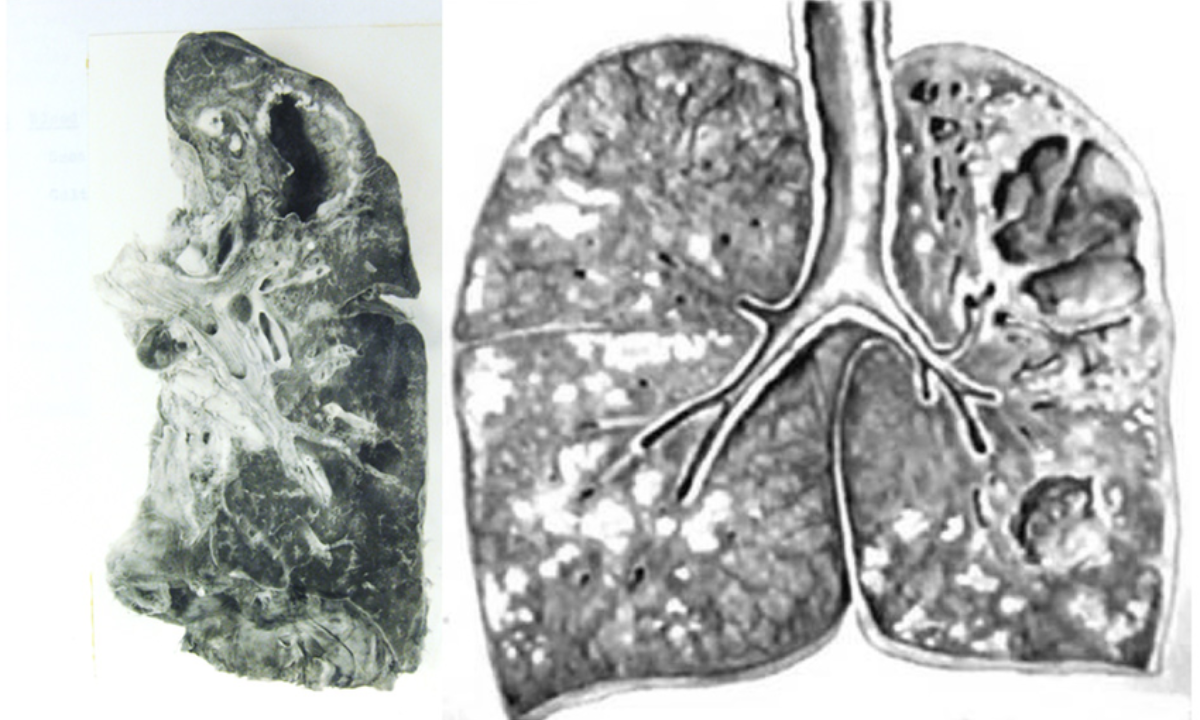

Pulmonary Tuberculosis Explained

Pulmonary tuberculosis refers specifically to TB infection in the lungs. It is the most common and most contagious form.

The bacteria damage lung tissues over time. If untreated, it can cause serious breathing problems and even spread to other organs.

4. Imaging Tests

Imaging helps detect lung abnormalities.

A CT scan gives a clearer picture of lung damage and complications.

Role Of Imaging In TB Diagnosis

Imaging plays an important role in confirming TB, especially pulmonary tuberculosis.